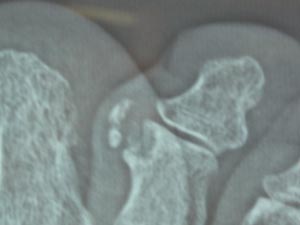

「そんなら、もしかしてこっちもですか。」と右足の第2指(ひとさしゆび?)も診てもらう。こっちはもっとひどい。木っ端みじんになっている。もうかれこれ30年ほど曲がったままで、少し痛い。

「珍しいから、また見せに来てください。私も調べておくから。」と言うことになった。ウ〜ム、大きな病院で診てもらった方が良いかも。